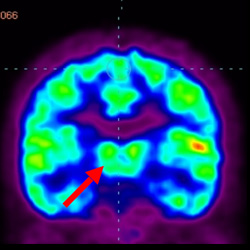

細(xì)胞治療后,藍(lán)色和黑色區(qū)域減少,并且看到更活躍的區(qū)域。這表明損傷減少并改善了大腦功能。

這證明細(xì)胞療法是治療腦癱兒童安全有效的方法。細(xì)胞療法可以更新大腦損傷的核心,并且可以通過 PET CT 掃描來監(jiān)測大腦的改善情況。這些細(xì)胞療法與標(biāo)準(zhǔn)治療一起促進(jìn)腦癱兒童的生長和改善。